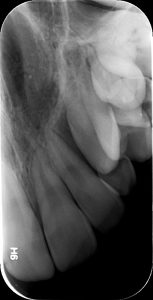

Η οπισθοφατνιακή ακτινογραφία λαμβάνεται με την τοποθέτηση του ακτινογραφικού πλακιδίου εσωτερικά των δοντιών (προς την πλευρά της γλώσσας ή του ουρανίσκου) και παράλληλα με αυτά. Χρησιμοποιείται ειδικός συγκρατητήρας του φιλμ, τον οποίο δαγκώνει ο εξεταζόμενος. Με αυτή απεικονίζονται ένα ή περισσότερα δόντια (τόσο η μύλη, όσο και η ρίζα αυτών), καθώς και τμήμα του φατνιακού οστού που περιβάλλει τις ρίζες των δοντιών. Αποτελεί την πιο απλή οδοντιατρική ακτινογραφική απεικόνιση. Χρησιμοποιούνται τρία μεγέθη φιλμ ή πλακιδίου ανάλογα με την περιοχή που θέλουμε να απεικονιστεί, το μέγεθος του στόματος του εξεταζόμενου και την ηλικία του. Η λήψη της είναι γρήγορη (διαρκεί λίγα δευτερόλεπτα) και ανώδυνη.

Η οπισθοφατνιακή ακτινογραφία μεταξύ άλλων μας επιτρέπει:

• την ανίχνευση οδοντικών τερηδόνων, τον καθορισμό της έκτασης και του βάθους τους και της σχέσης τους με τον πολφό του δοντιού

• τη μελέτη των ριζών των δοντιών (αριθμός, μορφολογία και πιθανή κάμψη αυτών, ύπαρξη απορρόφησης ή κατάγματος)

• τη μελέτη του αριθμού, της μορφολογίας, του εύρους και της πορείας των ριζικών σωλήνων εντός των ριζών

• τη μελέτη των σκληρών ιστών του περιοδοντίου, δηλαδή του φατνιακού οστού που περιβάλλει και στηρίζει το δόντι και του περιοδοντικού συνδέσμου. Σε περίπτωση περιοδοντικής νόσου, καθορίζεται η εντόπιση, ο βαθμός και η φύση (οριζόντια, γωνιώδης) της απορρόφησης του φατνιακού οστού

• τη μελέτη του φατνιακού οστού της περιακρορριζικής περιοχής του δοντιού για ύπαρξη παθολογικών εξεργασιών (απόστημα, κοκκίωμα, κύστη κ.λ.π.)

• την ανίχνευση κατάγματος των δοντιών.